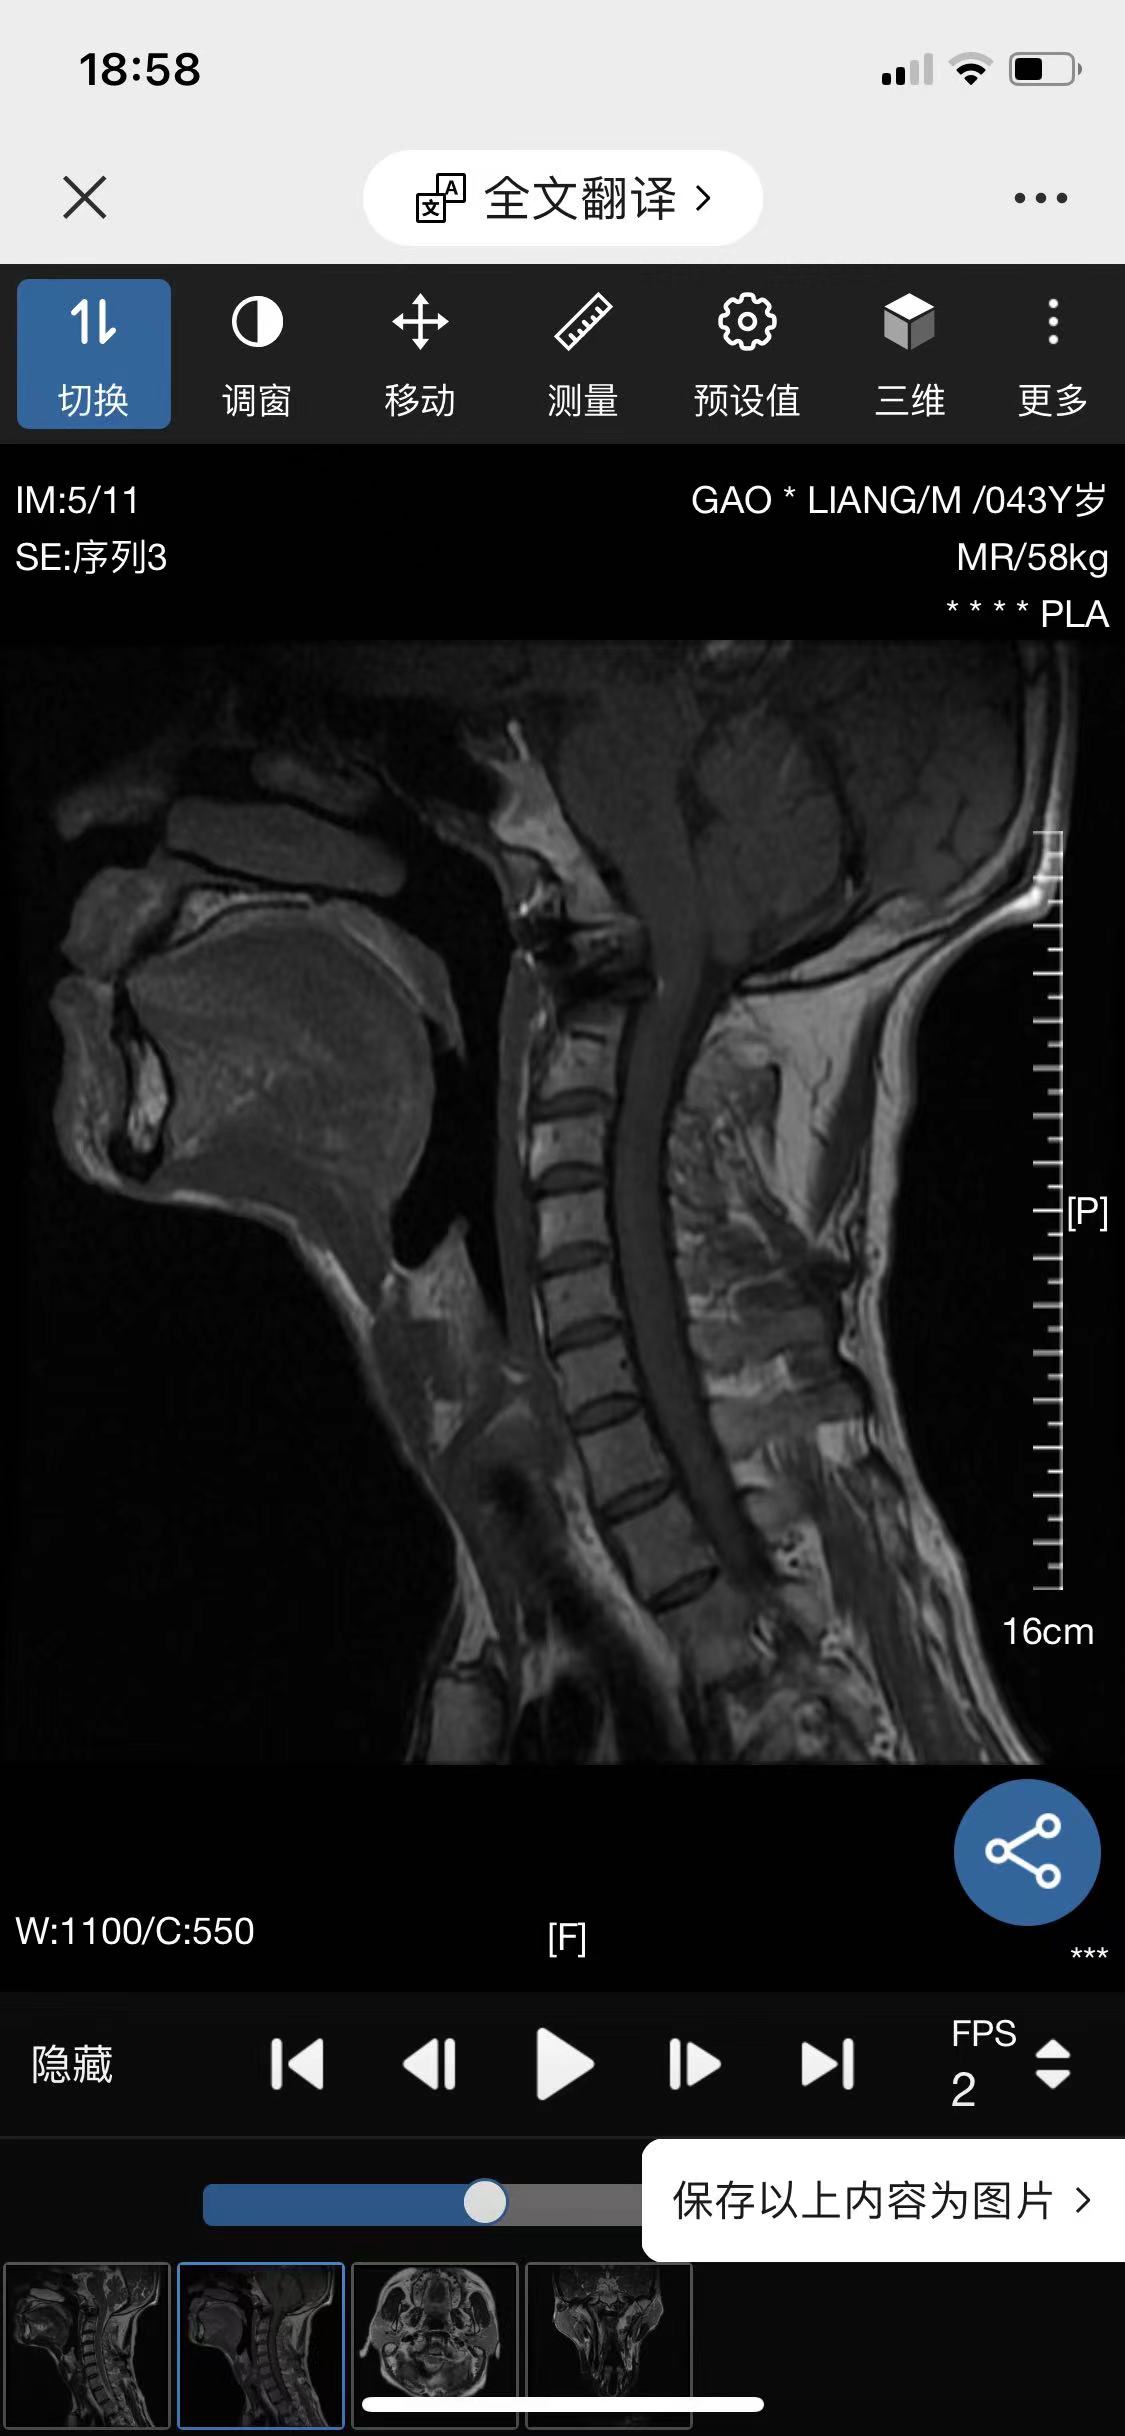

• 诊断:寰枢椎脱位

• 影像: